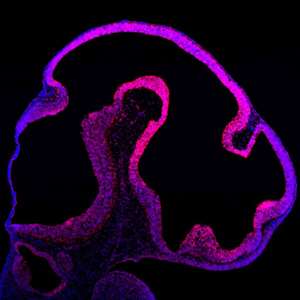

Immunohistochemical Staining with Polyclonal Antibody to Mouse Otx2 (Cat. No. M198) and DAPI. Tissue: Embryonic mouse, day 10 (E10), forebrain to midbrain. Fixation: 4% paraformaldehyde, 6 h. Permeabilization: 0.3% Triton X-100 in PBS. Blocking: 2% skim milk in PBS. Blue, DAPI stain; red, anti-Otx2 antibody.